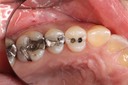

Photos of Clinical Operations

Mentors: Drs. Randy Allan, Greg Card, Peter Kearney

Clubs #44 and #50 joint meeting